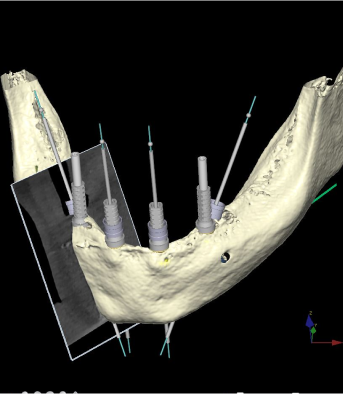

diagnostyka obrazowa a natychmiastowe obciążenie - zęby w jeden dzień

W nowoczensej stomatologii i implantoprotetyce diagnostyka oraz planowanie cyfrowe procedur medycznych bazuje na odwzorowaniu anatomii szczęk i żuchwy w obrazie CBCT, która jest podstawą projektów implantoprotetycznych dotyczących natychmiastowego obciążenia.

Tomografia stożkowa CBCT 3D bywa niezbędna w diagnostyce stomatologicznej przy planowaniu złożonych procedur chirurgicznych wymagających precyzyjnego zobrazowania anatomii strefy operowanej:– ekstrakcje zębów zatrzymanych, urazy, złamania, pęknięcia kostne– w implantologii określenie wymiarów wyrostka zębodołowego przed planowym zabiegiem umieszczenia implantu– w endodoncji określenie oboczności anatomicznych zębów przeznaczonych do leczenia kanałowego– w ortodoncji i ortognatyce przed analizą cefalometryczną w trójwymiarze – do precyzyjnego planowania zabiegów ortognatycznych

Drukarka 3D to nowoczesny i innowacyjny przyrząd do drukowania modeli przestrzennych w zadanej skali. Jej działanie polega na nanoszeniu warstwami specjalnego filamentu, który następnie jest utwardzany za pomocą światła lub wiązką laserową. Druk możliwy jest dzięki odpowiedniemu programowi, który przetwarza standardowe pliki z tomografu komputerowego i buduje cyfrowy model przestrzenny czytelny dla drukarki, która z kolei drukuje bryłę, odwzorowując nawet najdrobniejsze detale zeskanowanego obiektu. Precyzyjnie tworzy np. łuki zębowe, nakładki ortodontyczne, szablony chirurgiczne i inne akcesoria.